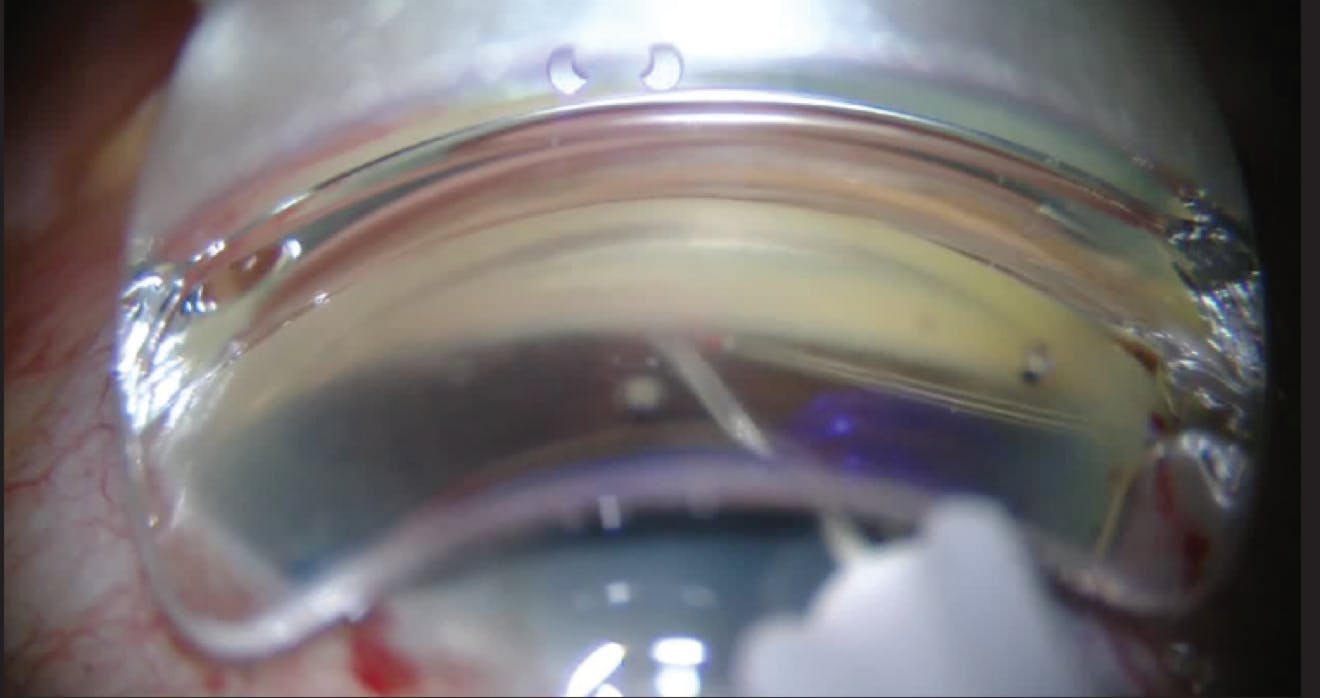

AB INTERNO CANALOPLASTY TRABECULAR MESHWORK PULL-DOWN TECHNIQUE

BILLY PAN, MD

CANAL SURGERY FOR GLAUCOMA

ARSHAM SHEYBANI, MD; IQBAL IKE K. AHMED, MD, FRCSC; STEVEN R. SARKISIAN JR, MD